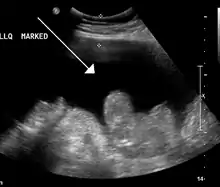

Ultrasound investigation is often done before attempts to remove fluid from the abdomen. This may reveal the size and shape of the abdominal organs, and Doppler studies may show the direction of flow in the portal vein, as well as detecting Budd-Chiari syndrome (thrombosis of the hepatic vein) and portal vein thrombosis. The sonographer also can estimate the amount of ascitic fluid, and difficult-to-drain ascites may be drained under ultrasound guidance. An abdominal CT scan is more accurate than a sonogram to reveal abdominal organ structure and morphology.[11]

- Grade 1: mild, only visible on ultrasound and CT